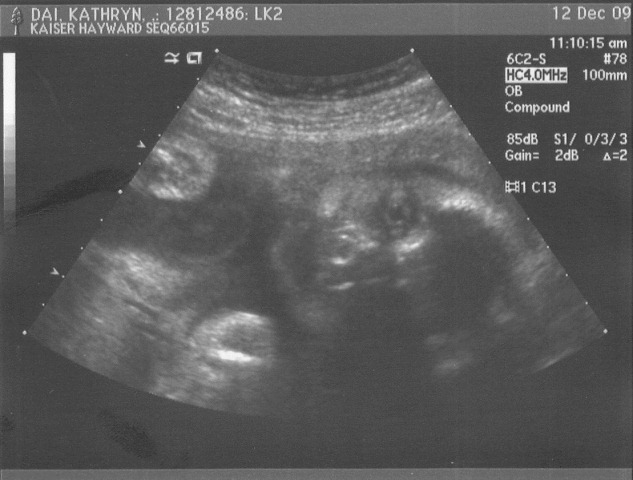

Day 308: baby face

At our ultrasound last Saturday, we got a gander at the baby’s face.

The detail and crispness of the image was amazing and a bit scary.

Here he is, staring at you:

Check out that massive eye!  It’s like he’s staring into your soul.